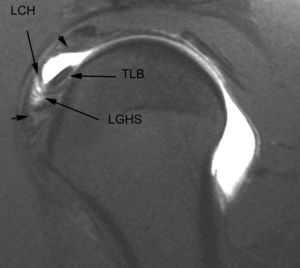

Lesiones del intervalo del manguito de los rotadores

El intervalo del MR es el espacio más o menos triangular localizado entre el borde anterior del tendón del supraespinoso y el borde superior del tendón subescapular. Este espacio anatómico está cubierto por la cápsula articular y contiene las siguientes estructuras (fig. 31): el LGHS, el LCH, el TLB y el borde anterosuperior del borde glenoideo. Los puntos de origen e inserción de estas estructuras se han descrito anteriormente, sin embargo es de notar que la relación entre el TLB y los LGHS y LCH, cambia a medida que estas tres estructuras se extienden desde sus puntos de origen hasta la zona proximal de la corredera bicipital (fig. 6). A nivel medial, aproximadamente a la altura de la articulación glenohumeral, el LCH se encuentra por encima del TLB y el LGHS se encuentra por delante de ambos. A nivel del troquiter el LGHS se coloca por delante y por debajo del TLB. A nivel de la parte proximal de la corredera bicipital, el LGHS se halla por debajo del TLB, mientras que el LCH permanece por encima del TLB. Esta distribución anatómica provee una estabilidad del TLB durante el movimiento del hombro (polea reflectora).

Fig. 31.--Intervalo de los rotadores. Artrorresonancia sagital oblicua T1 con supresión grasa, que revela el espacio entre el borde anterior del músculo supraescapular y el borde superior del músculo supraespinoso (cabezas de flecha). Dentro del espacio se encuentra, además de la cápsula, el tendón largo del bíceps (TLB), el ligamento coracohumeral (LCH) y el ligamento glenohumeral superior (LGHS).